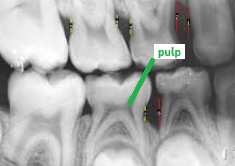

pulp

radiolucent